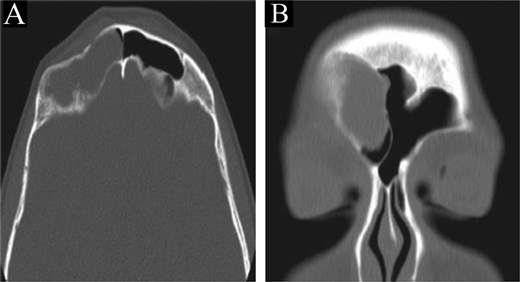

This is a 15-year-old male with no significant medical or surgical history who presented to our otolaryngology clinic with nasal discharge, mild headaches, and nasal itchiness. Preoperative CT scan of the paranasal sinus showed extensive disease with enlargement of the sinuses, predominantly on the right side (Fig. 3). MRI of the brain and paranasal sinus revealed similar findings, with right frontal sinus enlargement and intracranial extension, but intact dura.

CT scan of paranasal sinuses in (A) coronal and (B) axial views, showing extensive disease with enlargement of sinuses, with more expansion of the right frontal sinus.